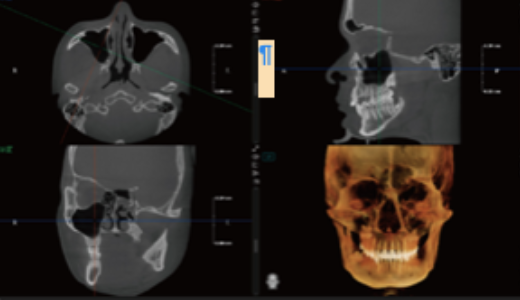

Planeamento Virtual de Implantes

Permite a simulação de procedimentos de implantes (implante + pilar + coroa), ajudando a selecionar o implante mais adequado.

Fornece alertas de proximidade ao canal nervoso, aumentando a segurança cirúrgica.

Facilita a comunicação entre médico e paciente, permitindo ao paciente visualizar claramente o procedimento de implante planeado.

Simulação de Extração Dentária e Óssea – Planeamento de Implante Imediato

Permite a extração do dente comprometido e a sua substituição por um implante adequado na simulação.

Melhora a comunicação entre médico e paciente, permitindo ao paciente visualizar o resultado final do implante antes da extração.